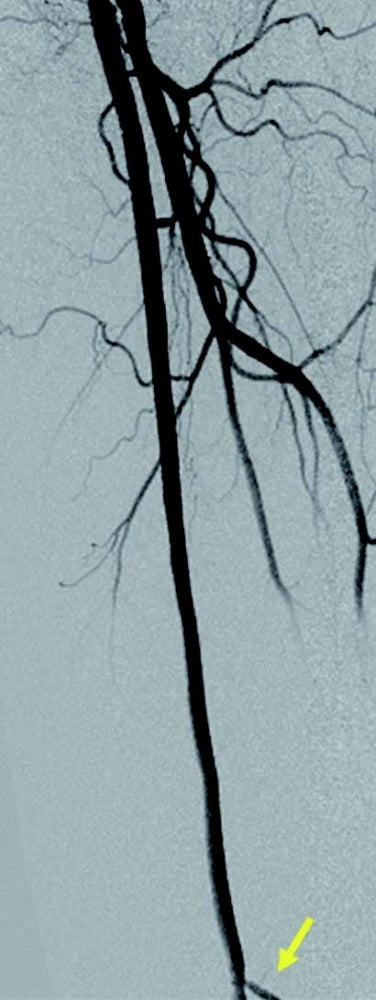

右浅大腿動脈閉塞(図3): 左鼠径部を穿刺(6 Fr シース)しcrossover後、順行性に0.014 inchマイクロカテーテルを使用して0.014 inch ガイドワイヤー(先端荷重1 g →3 g →40 g)を進めたが貫通できず、足背動脈を穿刺し逆行性に0.014 inch ガイドワイヤーを進め、貫通に成功。IVUS catheterで一部 subintimal trackingしていることを確認。5.0 mm 径バルーン(non-compliant balloon)で拡張後解離が生じ、末梢にバイアバーン® ステントグラフト5.0 × 150 mm、中枢に6.0 × 250 mm の2本を留置。病変の末梢には発達した2本の側副血行路を伴い、側副血行路の間に軽度狭窄病変を認めたため、中枢側の側副血行路をjailさせ、健常部にバイアバーン® ステントグラフトを留置。5.0 mm 径と6.0 mm 径バルーン(non-compliant balloon)で後拡張して終了。(図4)